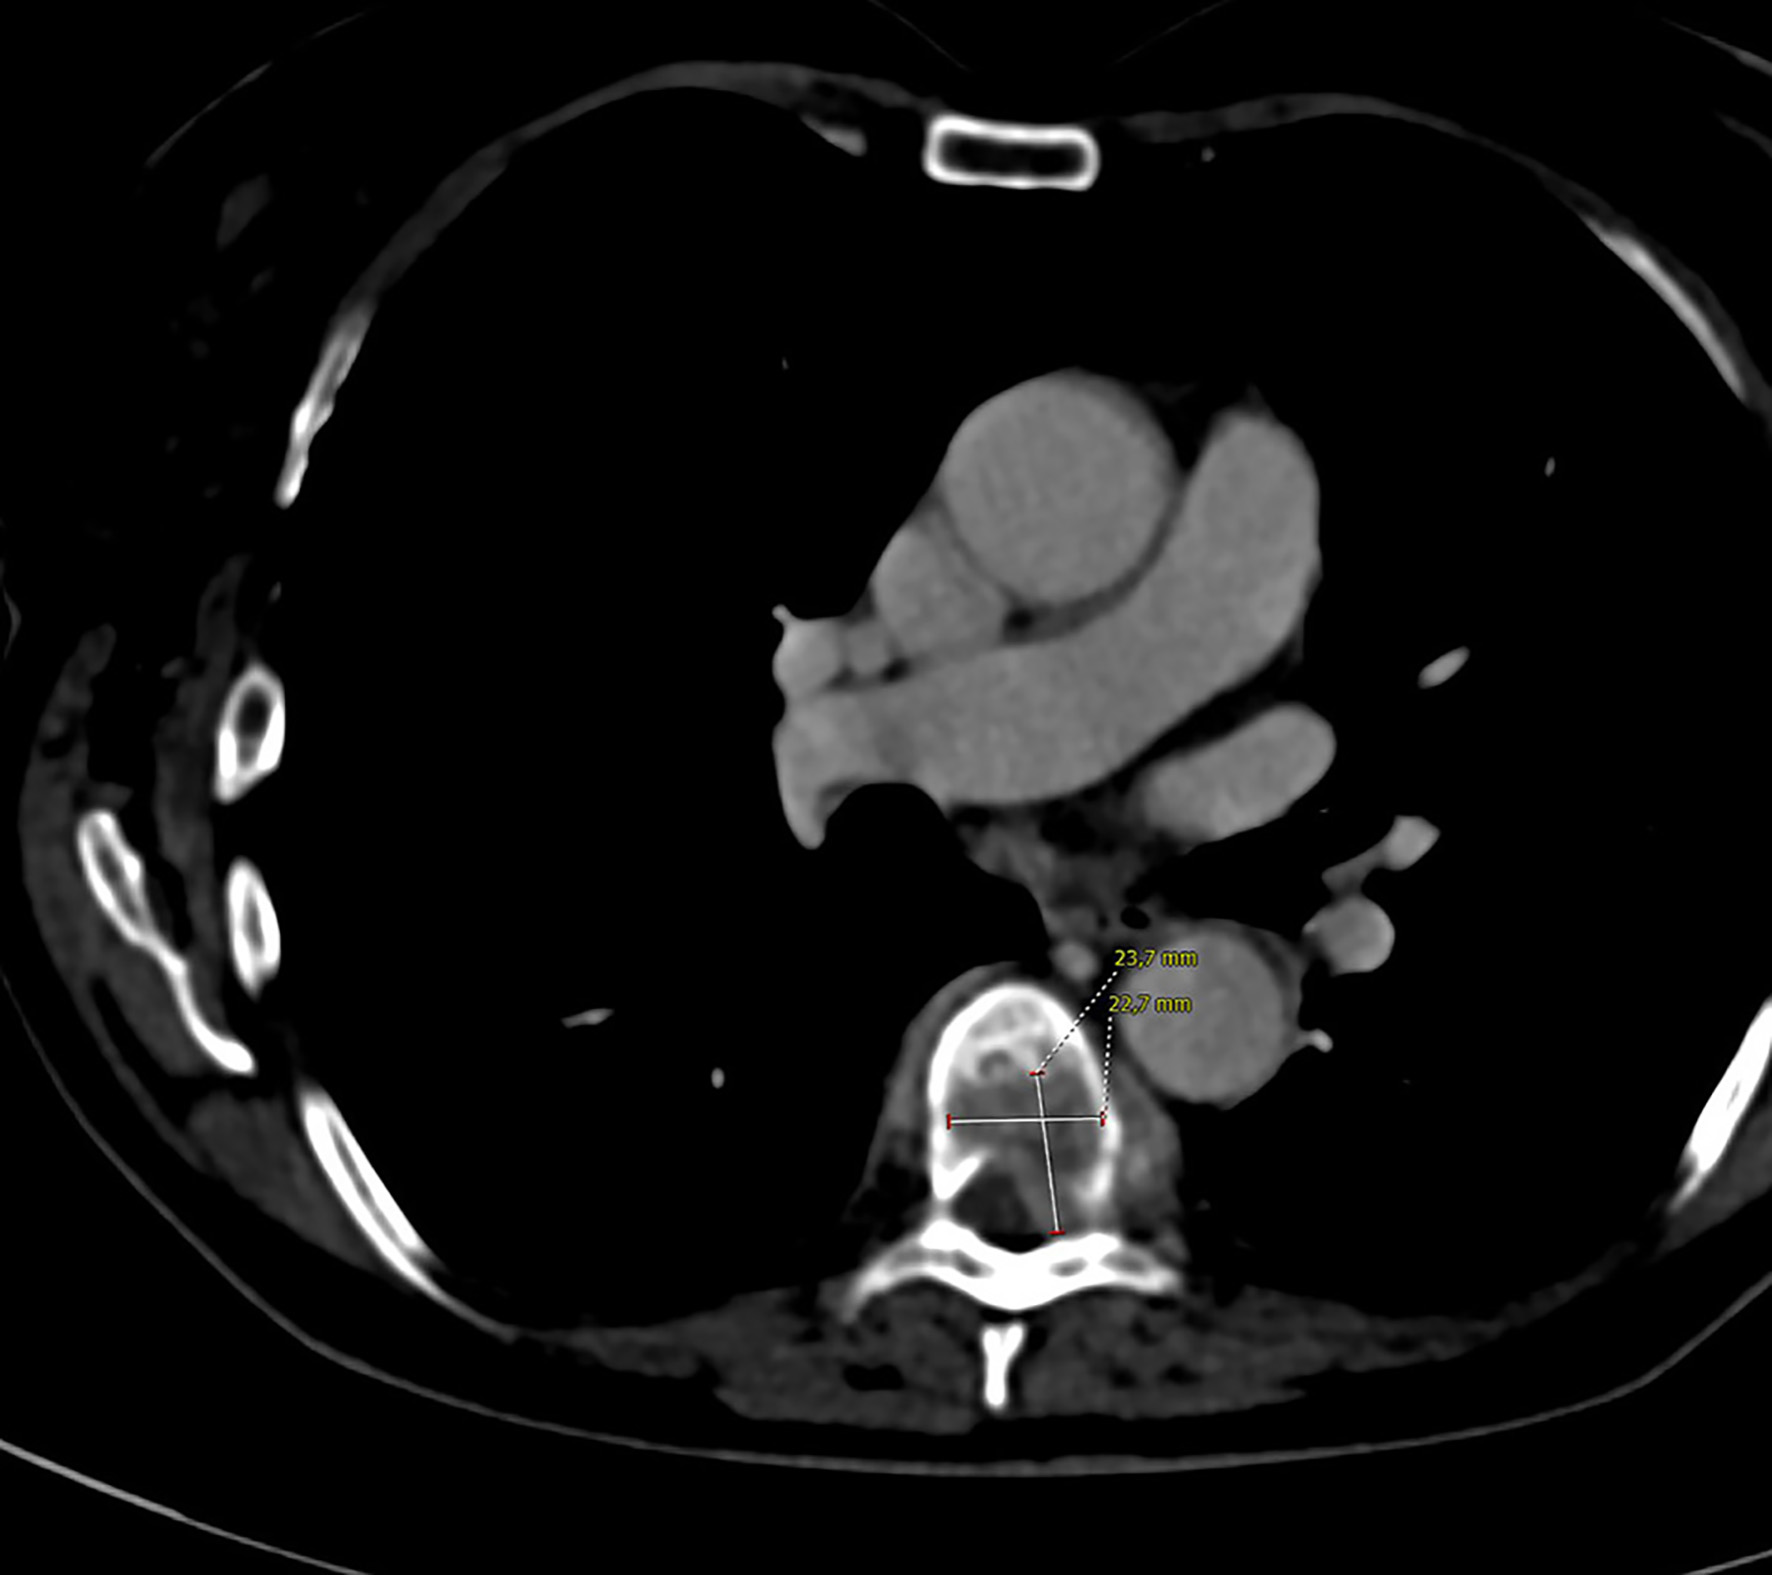

A 63-year-old female patient came to our attention for lower back pain. Her past medical history was significant for hypertension and pulmonary sarcoidosis treated with steroids. Neurological examination revealed a lumbar spinal syndrome without motor deficit. After failure of medical management, spinal computed tomography (CT) scan was performed, demonstrating a spinal lesion of 24 × 23 mm at the seventh thoracic vertebra (Fig. 1). A thoraco-abdomen CT scan revealed an 86 × 61 × 79 mm mass at the left kidney (Fig. 2) with multiple right pulmonary nodules and six bone lesions confirmed at the bone scan (Fig. 3). At diagnosis, Karnofsky Performance Status (KPS) was 80. The International Metastatic RCC Database Consortium (IMDC) risk score was intermediate and the Memorial Sloan-Kettering Cancer Center (MSKCC) score was intermediate. After multidisciplinary discussion, the patient underwent open trans-peritoneal left radical nephrectomy. The histology results described a ccRCC grade 2 with tumor extension in segmental (muscle-containing) venal branches and perirenal fat with clear margins (pathological T3aR0Nx). One month after surgery, she developed signs of spinal cord compression with neurological deficits and underwent emergency spinal decompression with a D7 laminectomy and stabilization of D5/D9. After neurosurgical operation and physiotherapy, she achieved complete remission of back pain and neurological deficits. A radiotherapy treatment of the vertebral metastases after surgery was avoided in order not to jeopardize complete functional recovery. The follow-up thoraco-abdomen CT scan after 3 months ruled out disease progression. She is currently on an immunotherapy regimen with avelumab (anti-programmed cell death-1 ligand, programmed death ligand 1) and axitinib (a vascular endothelial growth factor receptor TKI).

![]() Click for large image | Figure 1. Lumbar computed tomography scan revealing a spinal lesion of 24 × 23 mm at the seventh thoracic vertebra. |